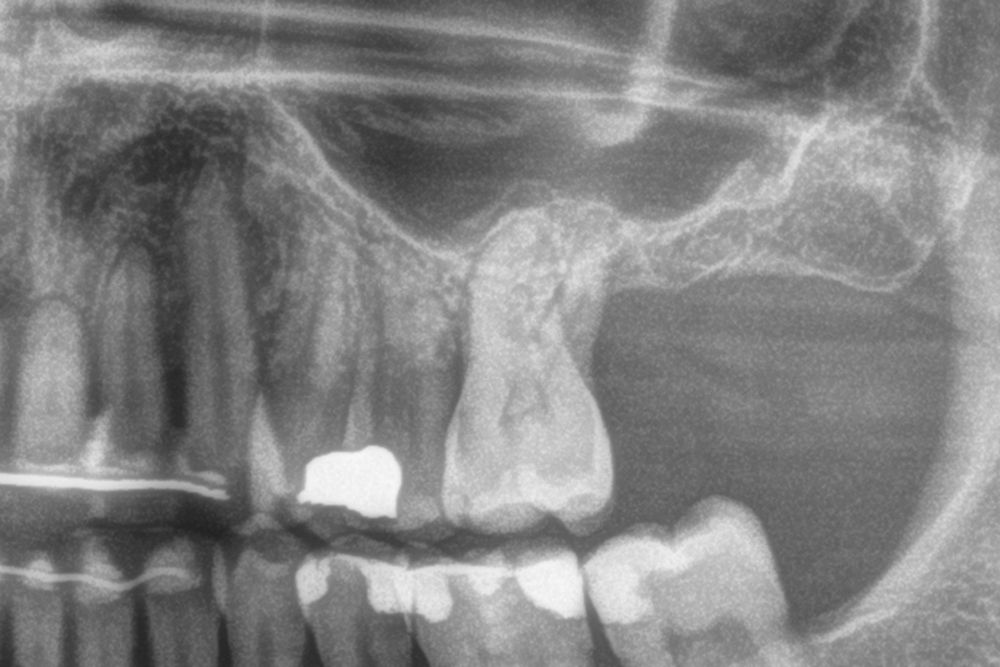

Material and method. A retrospective study has been carried out in patients in whom extra-short implants (4.5 and 5.5 mm length) were inserted directly by transcrestal elevation with residual ridges between 2 and 3 mm. The implant was the analysis unit for the descriptive statistics regarding location, implant dimensions, and radiographic measurements. The patient was the measurement unit for the analysis of age, sex and medical history. The main variable was the gain in height over the apex of the implant after 6 months of the surgery and one year after the load comparing both measurements and as secondary variables the biological complications and the implant failure were recorded.

Results. Ten patients who met the inclusion criteria were recruited and 20 implants were inserted. The mean residual bone volume height was 3.1 mm (+/- 0.3 mm with a range elevation above the apex of the implant in millimetres is of 2.8 mm (+/- 0.99 range 1.9 -5 mm). In the control cone-beam after one year of the studied load of the implants, the bone gain achieved was maintained, with no decrease in the volume gained, only three cases showed a decrease of between 0.4 and 0.5 mm of the initial volume at the end. No implants failed in the follow-up period and no biological complications were found in the surgery.

In this type of approach to the sinus, an important point is the stability of the grafted bone, located above the apex of the implant and with a bone tissue little vascularized (as usually occurs in these large atrophies with low density), so assessing what happens with the bone volume gained by this long-term procedure is also a key fact26,27. The mineralization of the bone graft and its maintenance once the implant loading is performed can make the difference in the success of the technique, especially in increasingly extreme cases. Therefore, the material used as a graft and the surface of the implant are two factors to take into account when performing this type of procedure28-31. Hydrophilic and osteoconductive surfaces in implants are of vital importance in these complex cases, as well as the filling materials that stimulate the formation of new bone28-31. The implants with UnicCa (Biotechnology Institute, Vitoria, Spain) surface, have a superhydrophilic surface. It is a very rough surface (Optima), with a calcium ions layer. This implies that the contact of blood and plasma with all points of the surface increases to the maximum the active surface for regeneration, by being completely coated with fluids due to its high capillarity. In the following series of clinical cases, patients treated by transcrestal sinus lift, with extra-short and ultra-short implants (4.5 and 5.5 mm), BTI (Biotechnology institute), of internal connection and universal plus platform in residual bone heights below 3 mm, studying the behaviour of implants regarding their survival as well as the maintenance of the bone volume achieved in the crestal elevation.